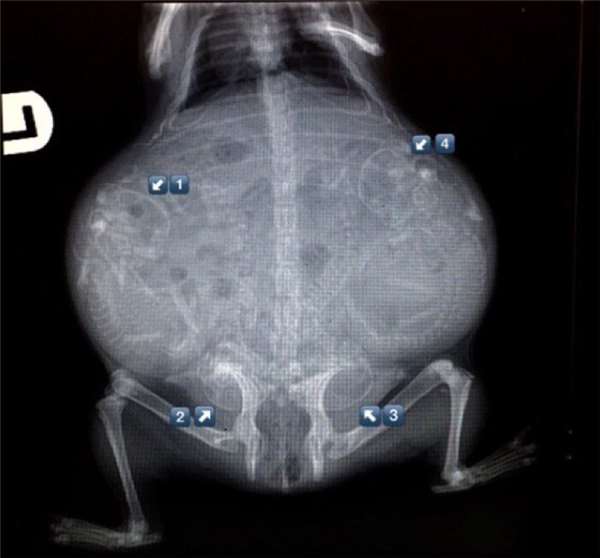

2.天竺鼠的,肚子大到不可思議

16.天竺鼠X光照